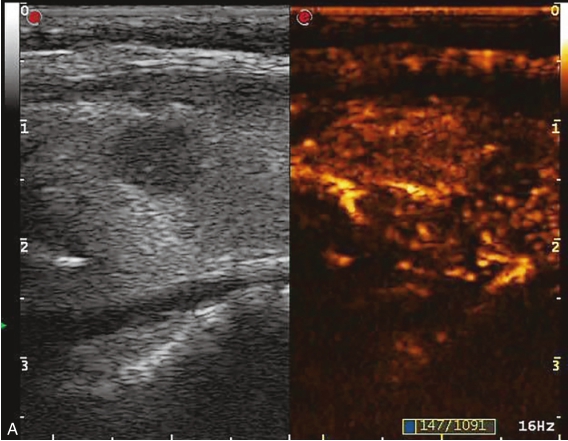

甲状腺右叶中上部见一低回声结节,大小约0.7cm×0.7cm×0.8cm,边界清楚,形态尚规则,内可见少许点状强回声。CDFI示结节内及周边可见较丰富血流信号,见图1-9-5。

图1-9-5 甲状腺髓样癌常规超声声像图

A.甲状腺右叶结节横切面;B.甲状腺右叶结节纵切面;C.甲状腺右叶结节CDFI血流图

甲状腺右叶上部结节超声造影后早于周围组织开始出现增强,达峰时呈偏低增强表现,边界不清,范围未见明显扩大,之后快速消退,晚期呈明显低增强,结节旁甲状腺被膜增强完整,见图1-9-6、ER1-9-3。

造影后结节内呈不均匀偏低增强表现,增强边界不清,增强晚期快速消退。

髓样癌体积较小时与乳头状癌的鉴别存在困难,内部丰富血流是髓样癌的主要特点,超声造影表现为中等偏低增强,与乳头状癌明显的低增强表现有别。

常规超声表现类似,超声造影后腺瘤常边界清楚,周边可见规则环状增强。实验室检查中降钙素、CEA升高对于髓样癌的确诊具有重要意义。